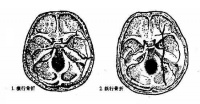

颞骨骨折

颞骨在受到暴力打击后可以发生骨折。耳道流血或外伤后颞部皮肤淤血,提示可能有颞骨骨折。若有清亮液体从耳道流出,可能发生脑脊液漏,提示大脑已暴露,易感染。颞骨骨折常伴有鼓膜破裂、面神经麻痹、重度感音神经性听力损失。通常CT可确定有无骨折。